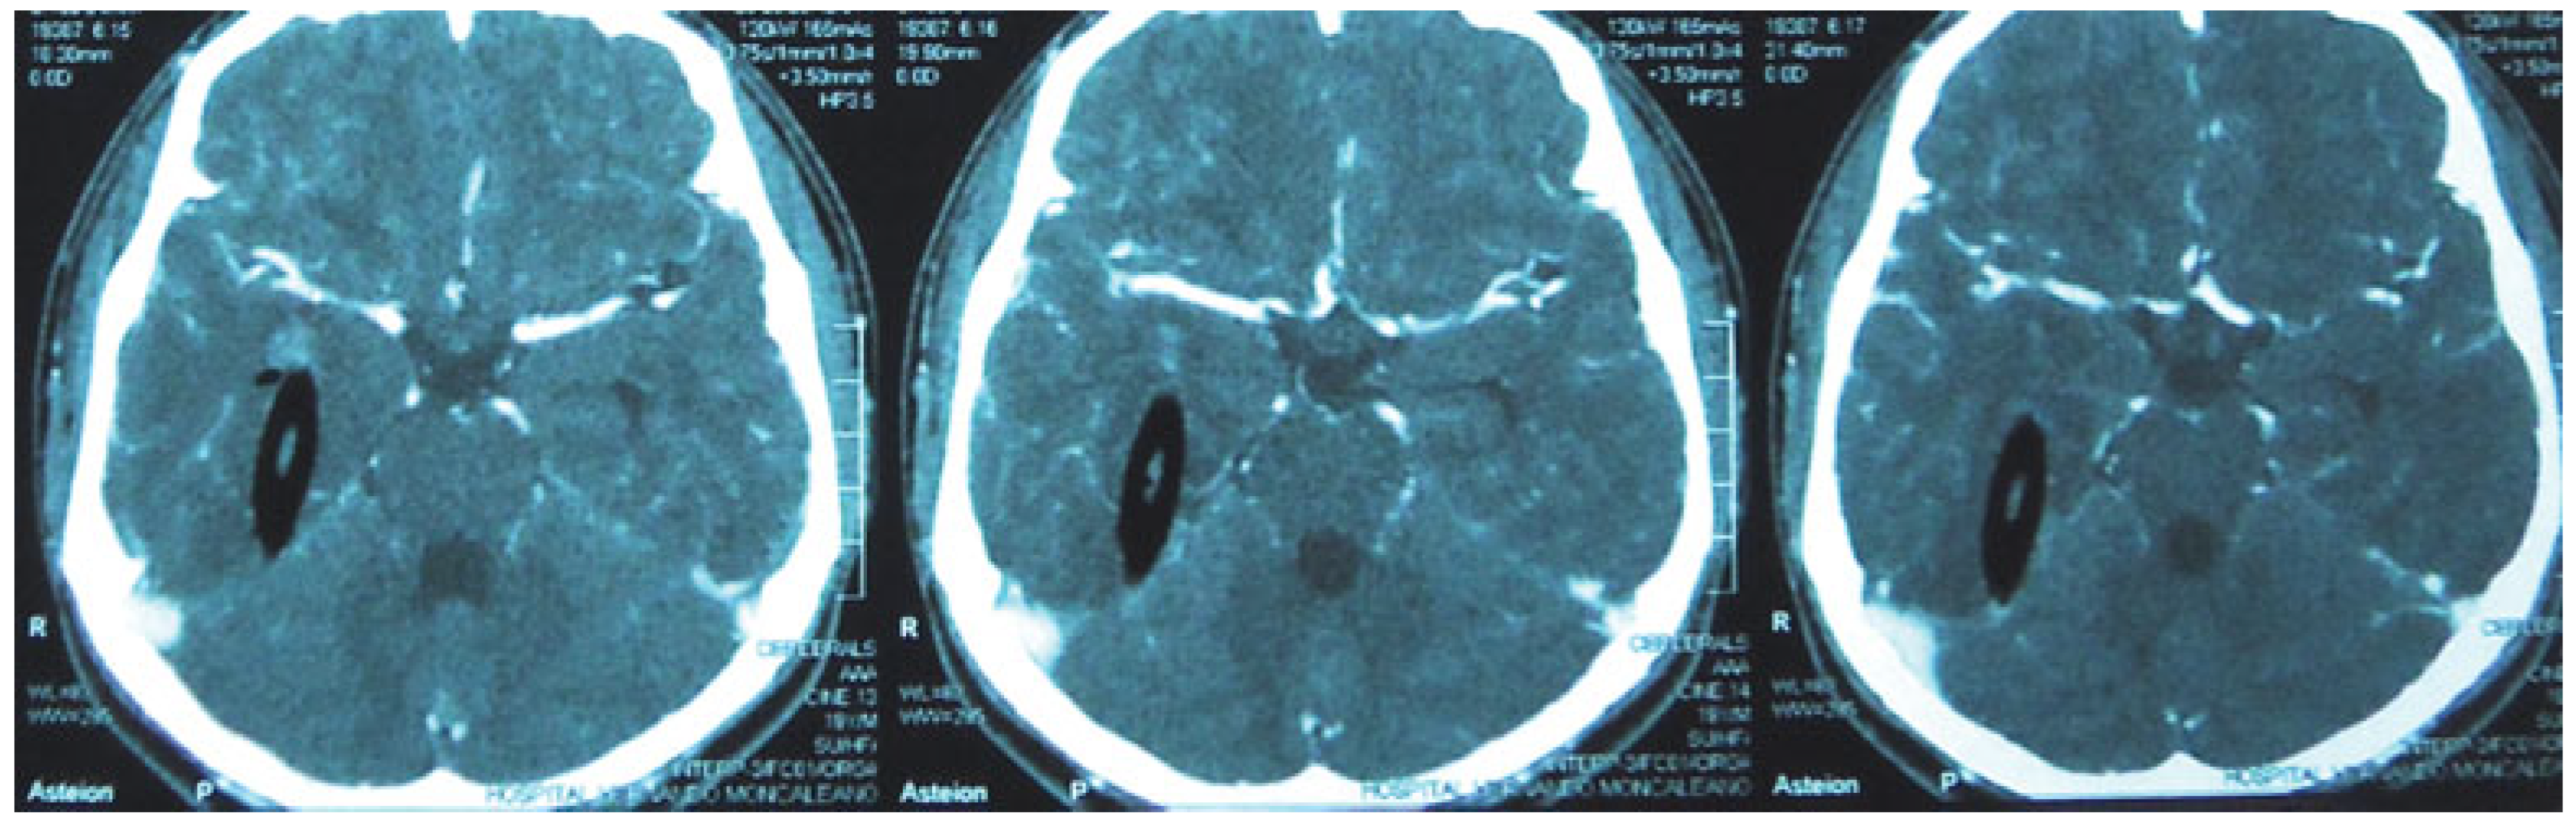

A 19-year-old man presented to the emergency department (ED) 3.5 h after suffering a penetrating injury to his right orbit following collision with a tree branch while running. On arrival at the ED, the patient’s vital signs were blood pressure (BP), 120/80 mm Hg; heart rate (HR), 82; respiratory rate (RR), 22; and GCS of 14. While in the ED, the patient’s GCS score deteriorated significantly to 7. Urgent cranial computed tomography (CT) demonstrated a fracture of the right orbit and associated penetration of a wooden fragment into the temporal and occipital lobes (Figure 1); however, no vascular injury was detected on CT angiography (Figure 2). Urgent craniotomy via a lateral orbital approach was undertaken and following isolation of the ipsilateral carotid artery, retrieval of the penetrating wooden fragment was performed with no significant bleeding. During the postoperative recovery on the intensive care unit, the patient developed an intracranial fungal infection and was treated with amphotericin B. The patient was discharged from the intensive care unit 11 days postinjury with a GOS score of 4 and total loss of vision on the affected side.

Figure 1.

A 19-year-old man with a penetrating injury to his right orbit with tree branch. The right temporal and occipital lobes were compromised.

Figure 2.

Computed tomography angiography showing the right MCA without vascular compromise. Abbreviation: MCA, middle cerebral artery.